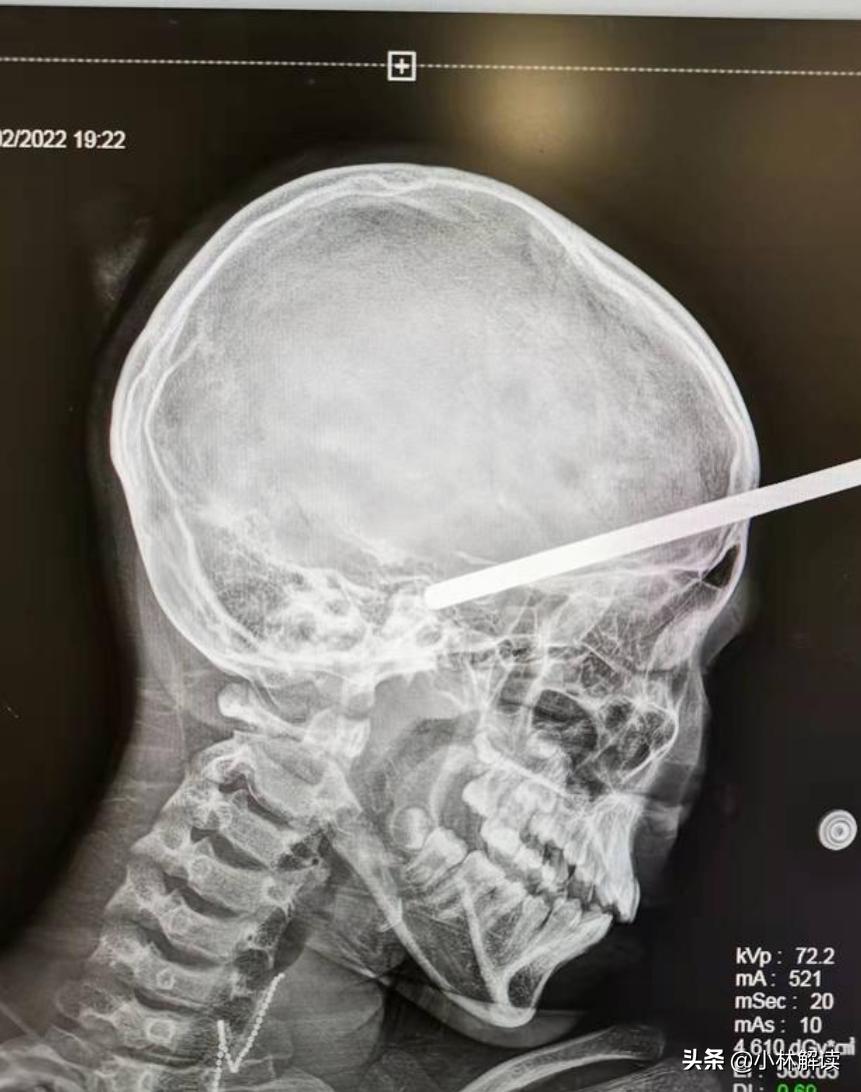

在2月2日,浙江嘉兴,一位10岁女童在跟妈妈、阿姨逛商场的时候,突然脚底打滑,迎面撞上了商场的货架,此时货架上悬挂商品的一根圆柱形空心铁棍直接插入到了女童的脑袋里。女童当时就因为疼痛而喊叫了起来,幸运的是女童意识仍然清楚,仍可以正常回答问题。

随后女童的家人们赶紧拨打了120,把女童送到上海交通大学医学院附属新华医院儿童神经外科进行治疗。

在女童送至医院后,当天的值班医生李奇峰和主治医生张海波为女童实施了微创开颅手术,取出了插入女童脑内的铁棍。